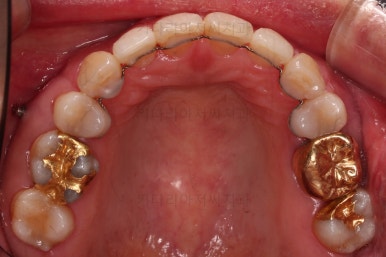

동래임플란트교정 초진 시 입안의 모습입니다.

임플란트가 이미 있을 경우

임플란트는 교정이 되지 않습니다.

뼈에 단단히 붙어 있기 때문에 힘을 줘도 원하는 위치로 이동되지 않습니다.

이번 환자분의 경우 임플란트가 어금니 크기보다 작게 제작이 되어 있어서 추후에 교합을 맞추기도 곤란한 상황이었어요.

그래서 교정 후에 임플란트 뿌리 부분은 그대로 사용하고 머리 부분만 재제작 하기로 했습니다.